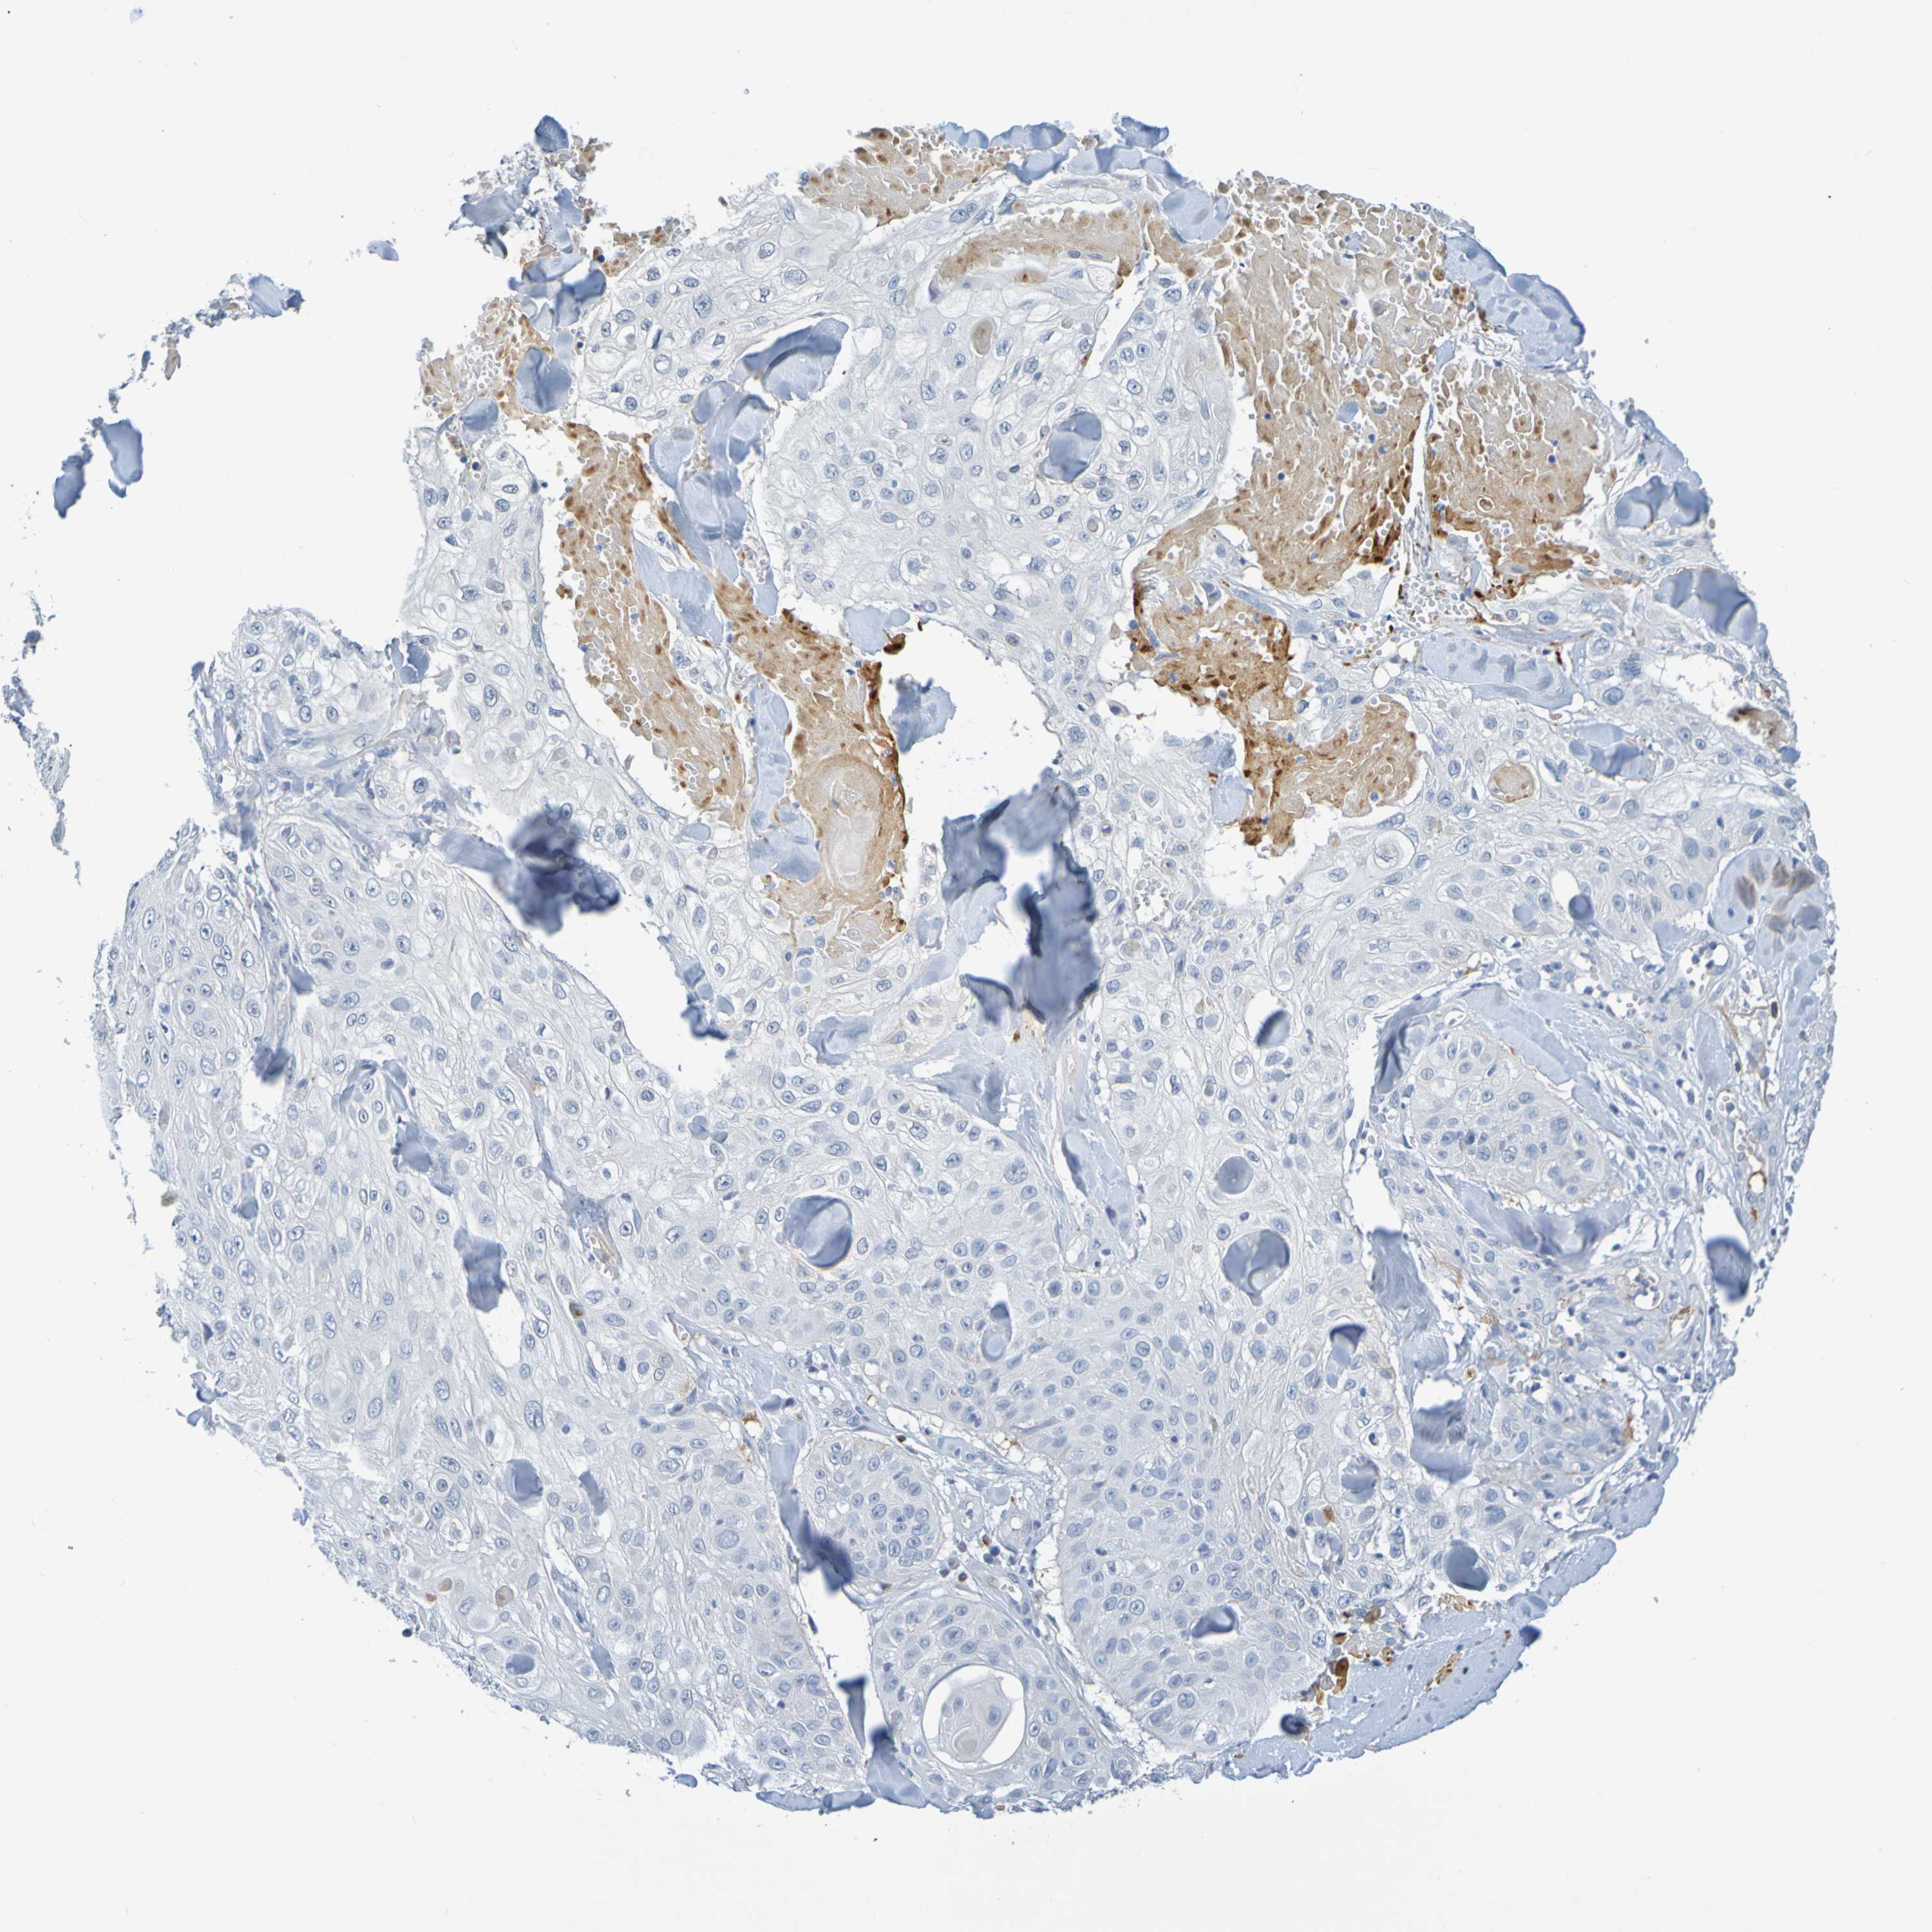

SKIN CANCER - Protein expressioni

A mouse-over function shows sample information and annotation data. Click on an image to view it in a full screen mode. Samples can be filtered based on level of antibody staining by selecting one or several of the following categories: high, medium, low and not detected. The assay and annotation is described here.

Antibody stainingi

Antibody staining in the annotated cell types in the current human tissue is reported as not detected, low, medium, or high, based on conventional immunohistochemistry profiling in selected tissues. This score is based on the combination of the staining intensity and fraction of stained cells.

Each image is clickable and will lead to virtual microscopy that enables deeper exploration of all samples and also displays staining intensity scores, fraction scores and subcellular localization as well as patient and tissue information for each sample.

Antibody HPA071391

Antibody CAB013120

Basal cell carcinoma

Squamous cell carcinoma, NOS